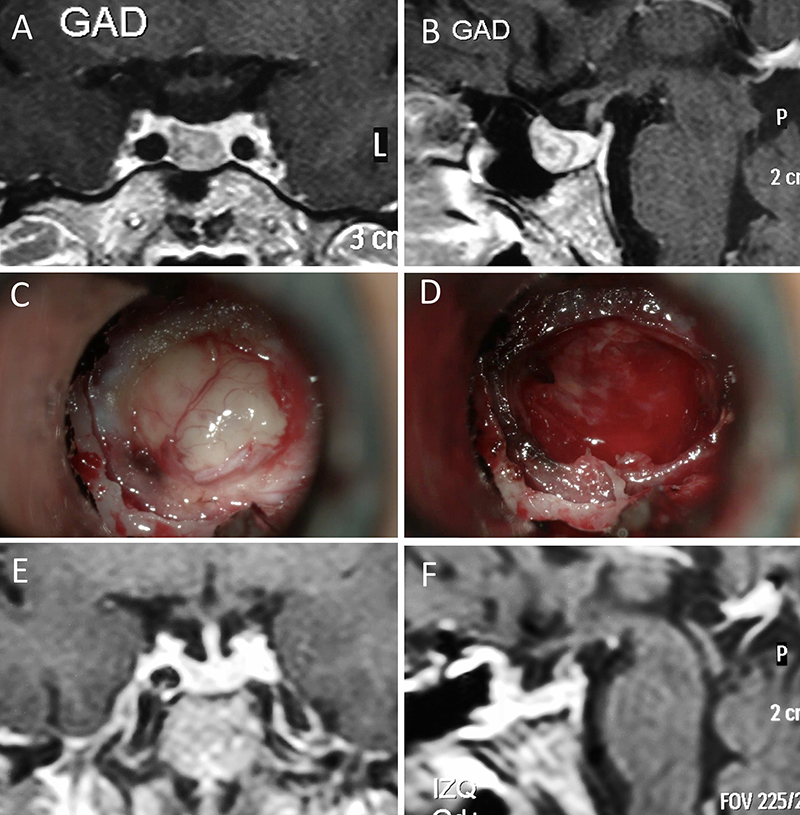

Figura 5: Apoplejía hipofisaria hemorrágica en un hombre de 32 años. El paciente presentó cefalea y parálisis completa del III par. Tuvo restitutio ad integrum en el seguimiento. A-B: RM preoperatoria; C-D: intraoperatorio; E-F: RM postoperatoria.

Figura 6: Apoplejía hipofisaria hemorrágica en un hombre de 55 años. El paciente presentó cefalea, déficit visual y parálisis completa del III par. Evolucionó favorablemente tras la cirugía, revirtiendo el cuadro. A-B: RM preoperatoria; C-D: intraoperatorio; E-F: RM postoperatoria.